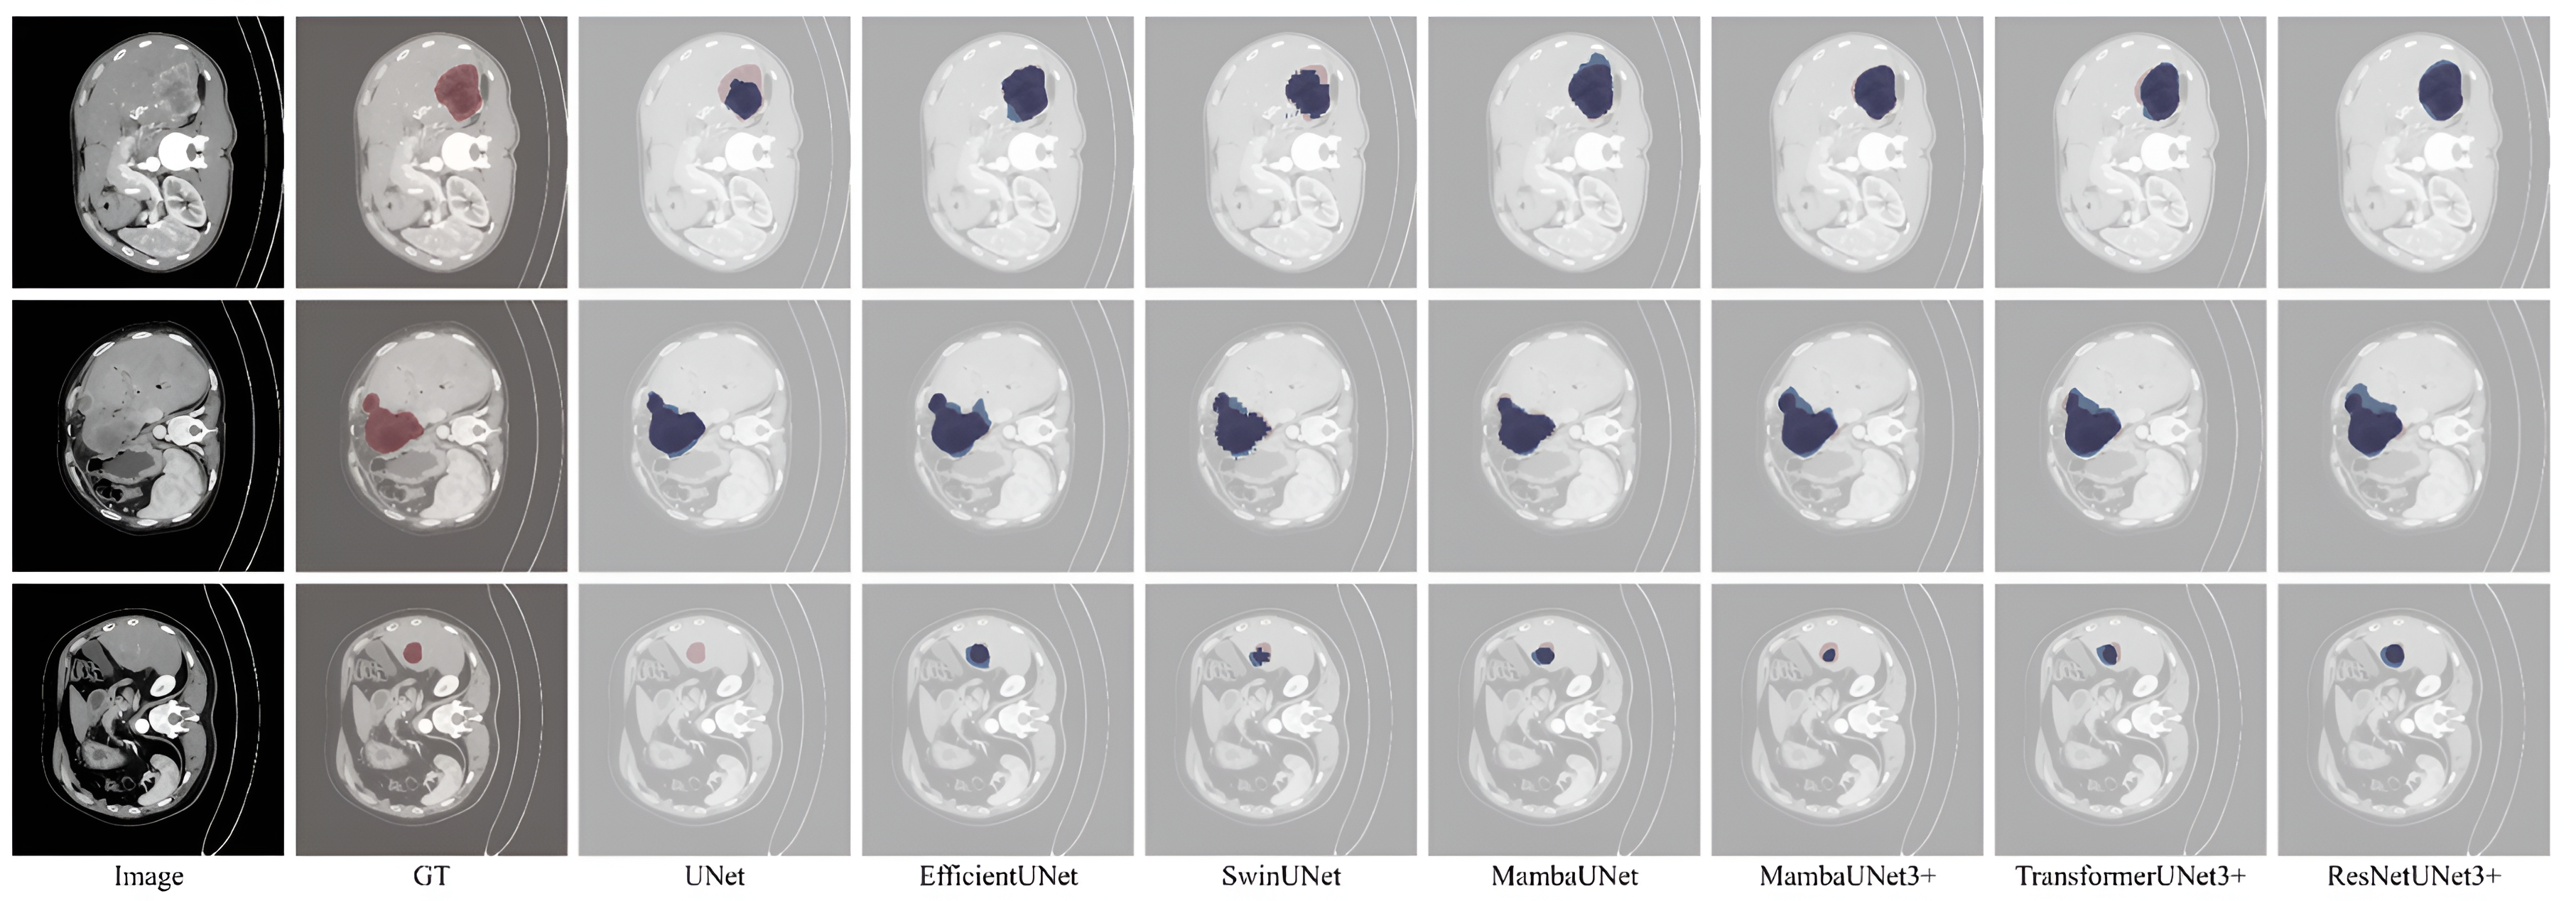

Refer to caption

Figure 6: The visual comparison of seven segmentation methods against ground truth on the testing set. The predicted and GT are highlighted in blue and red, respectively.

Predicted masks from the best-performing model, ResNetUNet3+, show more accurate tumor boundary delineation and fewer false positives compared to other architectures. Example cases illustrate both successful segmentations and challenging scenarios, such as small lesions or lesions adjacent to vessels, where performance remained limited. Visual comparisons highlight that ResNetUNet3+ with medium size of parameters (31.1 million) is more robust in capturing tumors than baseline UNet or Mamba- and Transformer-based alternatives as shown in Fig. 6.